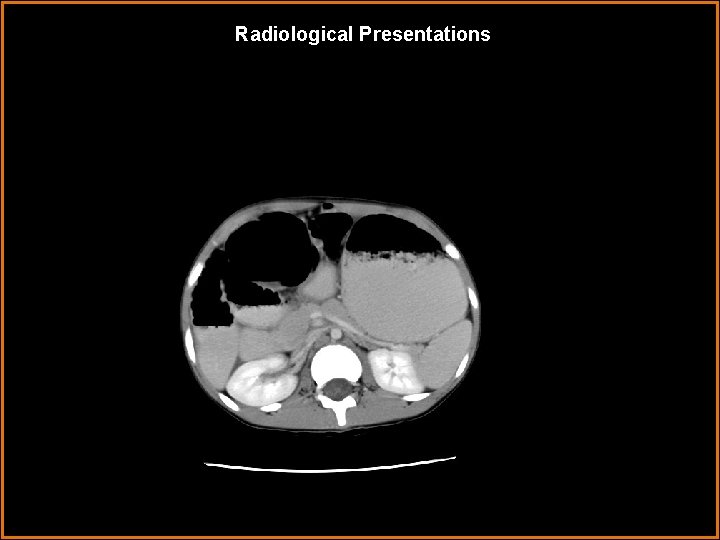

Radiological Presentations Axial contrast-enhanced CT

Findings and Differentials Duodenal and proximal jejunal loops wrap around the SMA/SMV, creating the “whirlpool” sign SMA/SMV

Findings and Differentials Dilation of distal SMV.